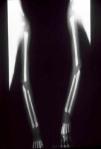

The early signs of nervous system involvement are meningitis and hydrocephalus, which may lead to mild to severe mental retardation or psychomotor disorders. The best known pulmonary complication is proliferative diffuse interstitial pneumonia, known as pneumonia alba.48 The kidneys are affected, and even in the absence of neurologic symptoms there may be cerebrospinal fluid (CSF) abnormalities. Most infants with apparently asymptomatic congenital syphilis have radiographic signs of osteochondritis or perichondritis, periostitis, and diaphyseal osteomyelitis (Figs. 12 and 13). The destruction of bone tissue may cause pain and fractures, leading to Parrot pseudoparalysis of an affected limb.48,49

Late manifestations of congenital syphilis are similar to those seen in the adult,15,16 except for the rarity of cardiovascular involvement in the child. Malformations (clinical stigmas) may develop, either because infection occurred at a critical growth stage or as a direct result of disease activity.50 Examples of stigmas related to infection during a growth phase include saddle nose (the apparent enlargement of the distal part of the nose compared to a depressed bridge) (Fig. 14), saber shin, poorly developed or poorly enameled incisors, and malformed molars. The most widely known inflammatory sign is interstitial keratitis, which usually manifests in the child as blurred vision, photophobia, and excessive tearing. When these signs have resolved, syphilitic retinitis may become apparent. Eighth nerve deafness usually manifests late and may be either unilateral or, more often, bilateral. Nystagmus and balance disorders may accompany deafness. When interstitial keratitis occurs with Hutchinson's teeth (Fig. 15) and deafness, the patient has Hutchinson's triad, which is highly predictive of a diagnosis of congenital syphilis, conferring the characteristic features of the disease. Linear rhagades may form around natural orifices (Fig. 16).15,16 At some point, gummas may develop on the iris, ciliary body, or intrinsic and extrinsic muscles of the eye. Other organs, such as the lungs may also become compromised (Fig. 17). Bone and muscle involvement may take the form of osteoperiostitis or painless symmetrical inflammation of the knees, a condition known as Clutton's joints. Soft palate gummas are late manifestations, developing during childhood in 1% to 5% of patients with congenital syphilis; such gummas tend to progress more rapidly in children than they do in adults. A characteristic form of diaphyseal osteomyelitis compromises phalanges, metacarpals, and metatarsals. Depending on whether gummas are treated early and successfully, they may or may not lead to perforations, cysts, pathologic fractures and multiple deformities that are highly painful (Fig. 18). Late manifestations appear after the preschool years, between the ages of 5 and 14 years. Periostitis and diaphyseal osteomyelitis, mainly involving the tibias, are usually found together. As these long bones soften, they arch, in a process which will persist in the phase of bone condensation and thickening and lead to so-called saber shins.51,52 The most characteristic signs and symptoms of congenital syphilis are summarized in Table 1, with emphasis on mucocutaneous features.53